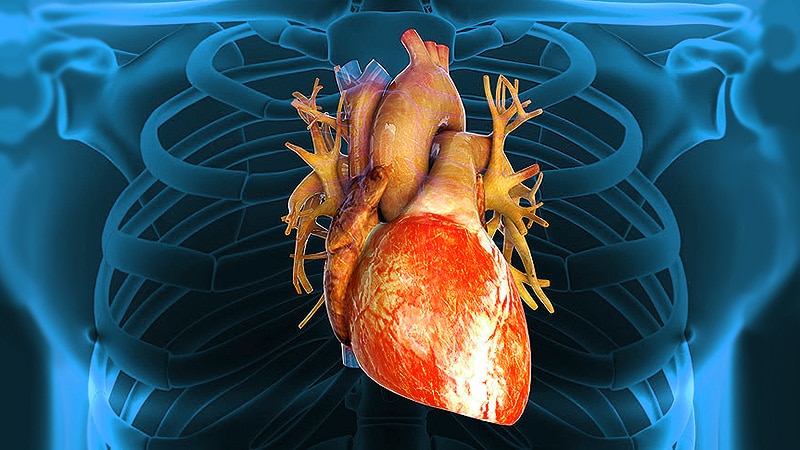

Анатомия здорового сердца: фотографии и иллюстрации

Раздел: Лаборатория идей